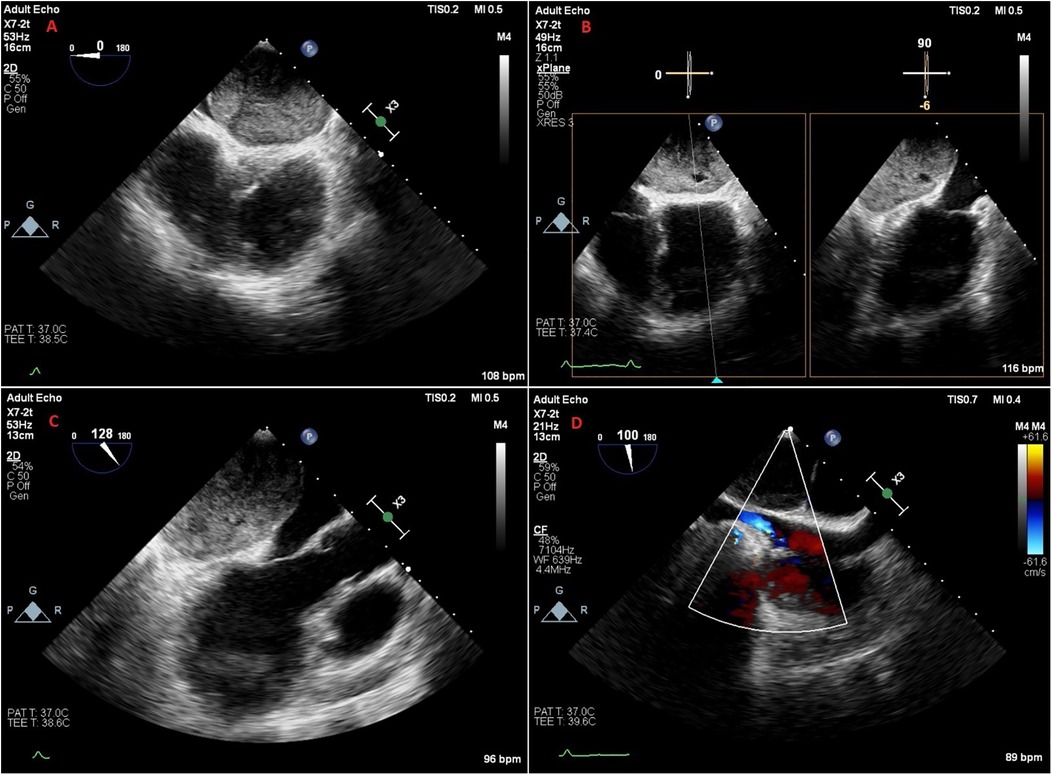

A 47-year-old female patient applied to the cardiology outpatient clinic with complaints of exertional dyspnea and intermittent chest pain. The patient's New York Heart Association (NYHA) functional capacity score was 2–3. Chest pain was unrelated to exertion. The patient had hypertension and was normotensive under perindopril 10 mg and amlodipine 10 mg treatments. She was a nonsmoker and had Class I obesity with a body mass index of 30.8 kg/m2. Physical examination was normal. Laboratory parameters showed an elevation of low-density lipoprotein at 187 mg/dl and an elevation of N-terminus pro-B-type natriuretic peptide (NT-proBNP) at 684 pg/ml. The electrocardiogram showed sinus rhythm with a rate of 83 bpm and no abnormalities. Transthoracic echocardiography (TTE) revealed a well-circumscribed hypoechoic mass lesion measuring 8.5 cm × 5.4 cm, located behind the posterior walls of the left atrium and left ventricle, causing significant compression of the left atrium (Figures 1A,B). Other findings of TTE were; normal left ventricular systolic function with a left ventricular ejection fraction (LVEF) of 65%, mild dilatation of the left atrium with a left atrial volume index (LAVI) of 36 ml/m2, mild mitral valve regurgitation, mild tricuspid valve regurgitation, tricuspid valve regurgitation velocity 3.2 m/s, grade II diastolic dysfunction and normal right ventricular systolic function with a tricuspid annular plane systolic excursion of 22 mm. Transesophageal echocardiography (TEE) was performed for detailed evaluation of the mass and its neighbors. TEE showed a mass containing a cystic lesion that caused significant compression of the left atrium (LA) and mild compression of the inferior vena cava (IVC) (Figure 2). No pulmonary venous return anomaly or obvious compression of the pulmonary veins was detected on TEE. Thoracic computed tomography (CT) angiography revealed a pericardial mass lesion measuring 10.1 cm × 8.1 cm × 5.2 cm in size, with regular borders and soft tissue density, located in the posterior mediastinum, adjacent to the LA and descending aorta, creating significant compression on the esophagus (Figure 3). The whole-body 18F-fluorodeoxyglucose (18F-FDG) positron emission tomography (PET)-CT images revealed a giant pericardial mass with mild to moderate 18F-FDG avidity (Figure 4). No metastatic lesions were detected. Magnetic resonance imaging (MRI) showed a well circumscribed, T1-hypointense and T2-hyperintense pericardial mass. The mass was observed to have homogeneous signal intensity on T1 and T2-weighted images. There was no direct myocardial infiltration and/or left atrial invasion (Figure 3). Contrast-enhanced images were not obtained for the patient who had a history of anaphylactic shock due to a gadolinium-based contrast agent. CT and MRI showed that the mass did not cause myocardial involvement, however, the mass could not be demarcated from the LA and IVC. The coronary angiogram did not detect obstructive coronary artery disease or coronary artery compression due to the mass. For the histological diagnosis of this giant pericardial mass, EUS-FNA was performed. Histological evaluation revealed foci of spindle cell proliferation forming Antoni A and Antoni B areas. Immunohistochemical studies revealed that these spindle cells stained diffusely positive for S100, which was consistent with schwannoma. The Ki-67 index was less than 1%.

Figure 1

Figure 1. Transthoracic echocardiography images of the patient. (A,B) Apical 2-chamber (A) and apical 4-chamber (B) views of a hypoechoic mass located posterior to the left atrium and left ventricle, and compressing the left atrium. (C,D) Apical 2-chamber (C) and apical 4-chamber (D) views of the patient at one year follow-up, showing that the mass was successfully removed.

The patient's in-hospital follow-up was uneventful, and she was discharged on the 9th postoperative day. No mass was detected in the patient's echocardiographic follow-up (Figures 1C,D). The patient's NYHA score was 1 at 6-month follow-up, and she had no chest pain. PET-CT showed no residual lesion or metastasis. TTE performed at 1-year follow-up revealed that LVEF was 65%, LAVI (30 ml/m2), and diastolic functions were normal. At 1-year follow-up, NT-proBNP was normal, and the NYHA score was 1.